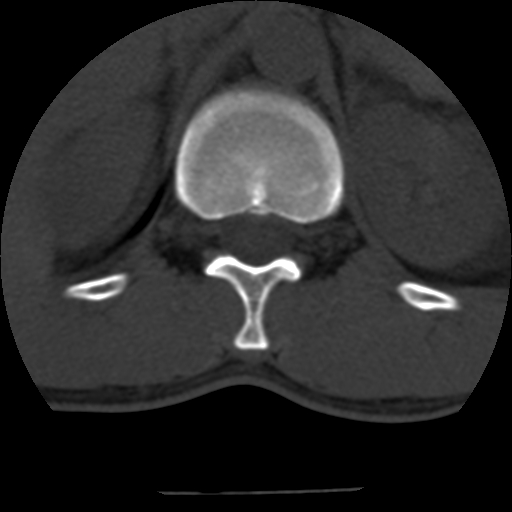

男,31岁,从6米高处坠落伤两天,腰背部疼痛,临床要求ct扫描胸10-腰1。请大家帮忙看看骨质有问题吗?

t12、l1锥体前缘轻度楔形变,平扫示椎体前缘骨小梁欠规整,第9幅图示椎体前缘骨质不连续,结合外伤史考虑椎体轻度压缩骨折。

从上查骨窗第九片椎体前缘皮质显示断裂.压缩骨折?

楼主扫描层厚可能较大,每个椎体只有三个层面.

从所示层面分析,无明确骨折征象,象类似病人我个人会建议mri除外骨挫伤.